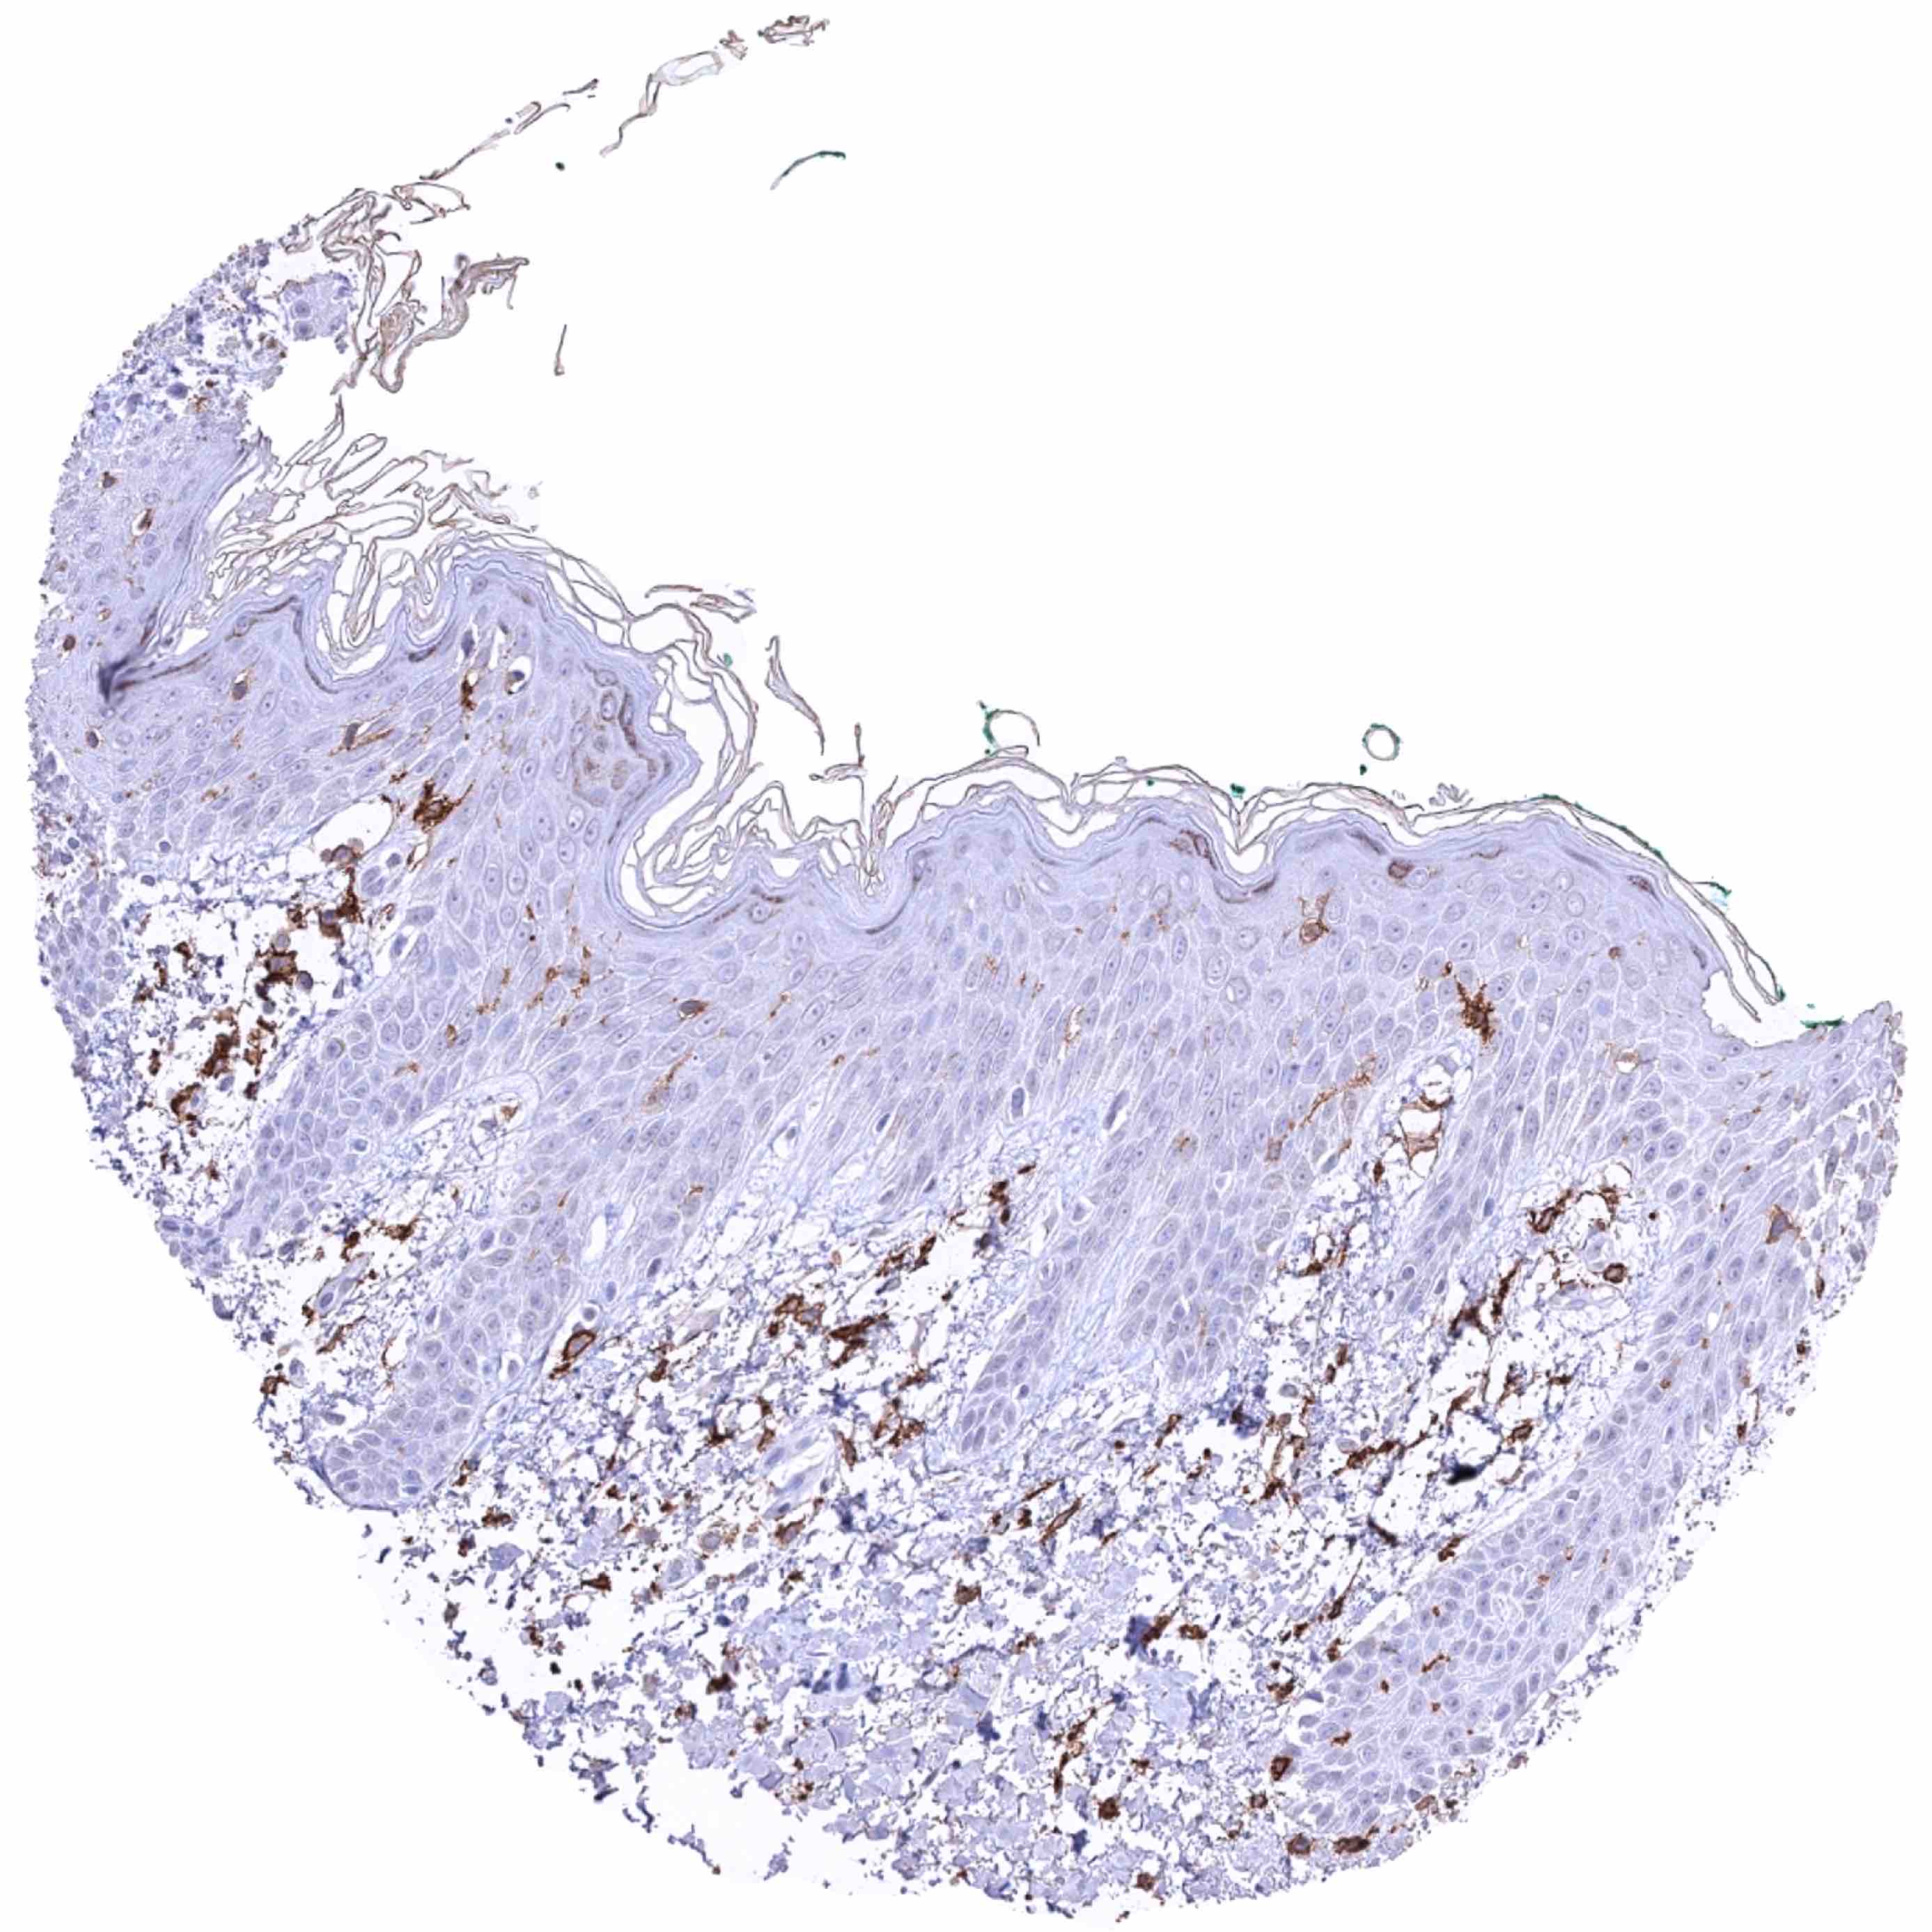

Skin – Distinct CD38B staining of intraepidermal dendritic cells (Langerhans cells). Other inflammatory cells are also CD38B positive

Skin